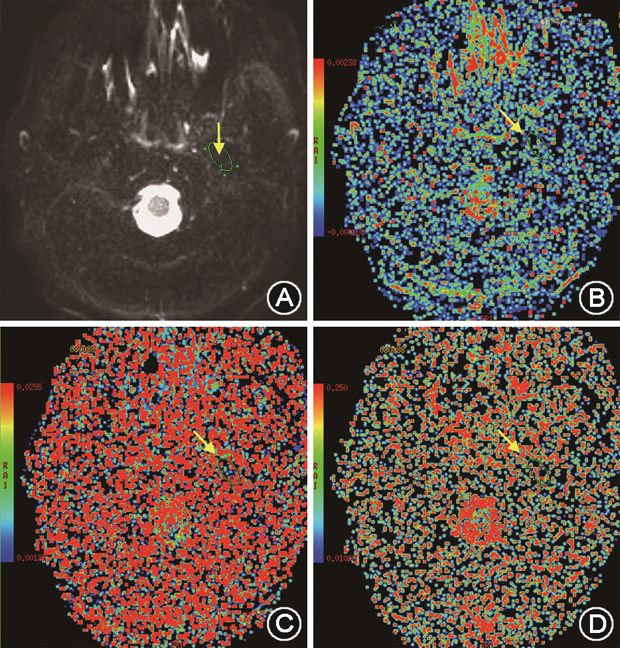

体素内不相干运动(intravoxel incoherent motion,IVIM)成像是一种通过多个敏感扩散因子(b)数值(图6A)及双指数拟合的DWI成像技术[17, 18],主要参数包括:①慢弥散系数D,反映真实的弥散信息,代表实际弥散对弥散信号衰减的贡献(图6B);②快弥散系数D*,反映的是灌注信息,又称灌注系数,代表灌注对弥散图像信号衰减的贡献(图6C);③灌注分数(perfusion fraction,f),反映了血流量(图6D)。研究发现不可复性关节盘移位患者的翼外肌上头血流灌注分数较关节盘位置正常者显著增高[18],反映局部血容量增多,提示炎症反应;而伴有颞下颌关节骨关节炎患者的翼外肌上头及下头的水分子扩散参数D均显著增高,可能是由于肌肉萎缩导致的细胞外间隙增宽所致。这两个参数在一定程度上反映了肌肉的病理改变。

注:箭头指示感兴趣区